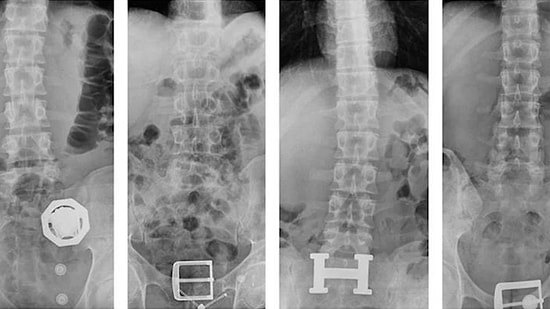

Günümüzde aşı karşıtı aileler yeni doğan bebeklere yapılan kızamık, kabakulak ve suçiçeği gibi aşıları yaptırmamayı tercih ediyor. Çünkü bebeğin önlenebilir hastalıkların ortaya çıkışını engellemek, bu hastalıklardan kaynaklanan ölümler ve sakatlıkları önlemek amacıyla yaptırılan aşılar hakkında ölüme yol açan asıl sebep olduğuna inanıyorlar. Bu nedenle yeni doğandan topuk kanı dahi aldırmayan bir aile yaşadıklarını sosyal medyada anlattı.